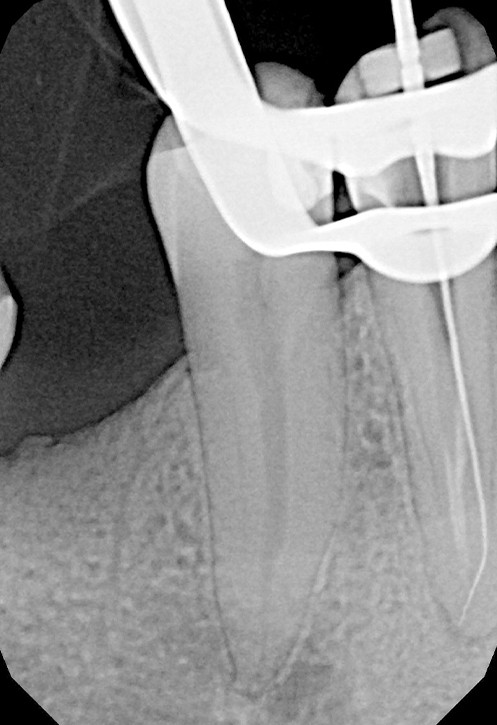

Podstawowym narzędziem diagnostycznym podczas leczenia jest endometr, elektroniczny miernik długości kanału, którym w trakcie procedury wykonuje się pomiary oraz potwierdza stopień drożności kanału.

Na podstawie zdjęcia rentgenowskiego określa się kształt i długość kanału bądź za pomocą specjalnego urządzenia mierzy się jego długość. Potem lekarz otwiera wejścia do kanału, chroniąc ząb koferdamem, czyli specjalną gumą, zapewniającą sterylność oraz chroniącą przed środkami chemicznymi służącymi do oczyszczania kanału. Używa się do tego zarówno specjalistycznego sprzętu, jak i nowoczesnych mikroskopów, pozwalających na uzyskanie dokładnego obrazu leczonego zęba. Ostatnią czynnością jest wypełnienie materiałem światłoutwardzalnym i zabezpieczenie zęba przed dostaniem się i rozwojem bakterii mogących wywołać wtórny stan zapalny.

Leczenie pod mikroskopem nie różni się znacząco od standardowych technik. Pacjent zawsze pozostaje w pozycji leżącej i jest zaopatrzony koferdamem. Koferdam to gumowa ochrona zabezpieczająca pacjenta przed połykaniem drażniących płynów dezynfekujących kanały korzeniowe. Chroni również kanał korzeniowy przed wtórnym infekowaniem ich śliną. Powiększony obraz uzyskany w optyce mikroskopu poprawia precyzję i przyspiesza pracę endodoncie.

Leczenie kanałowe zęba „martwego” nie różni się szczególnie od leczenia zęba „żywego”. Zabieg jest z reguły bezbolesny, ponieważ ząb pozbawiony jest reakcji bólowej ze strony ukrwionej i unerwionej tkanki – miazgi, znajdującej się w jego komorze i kanałach. Dla poprawy komfortu pacjenta oraz pracy można znieczulić jedynie dziąsło z uwagi na manipulacje przy zakładaniu klamry koferdamu.